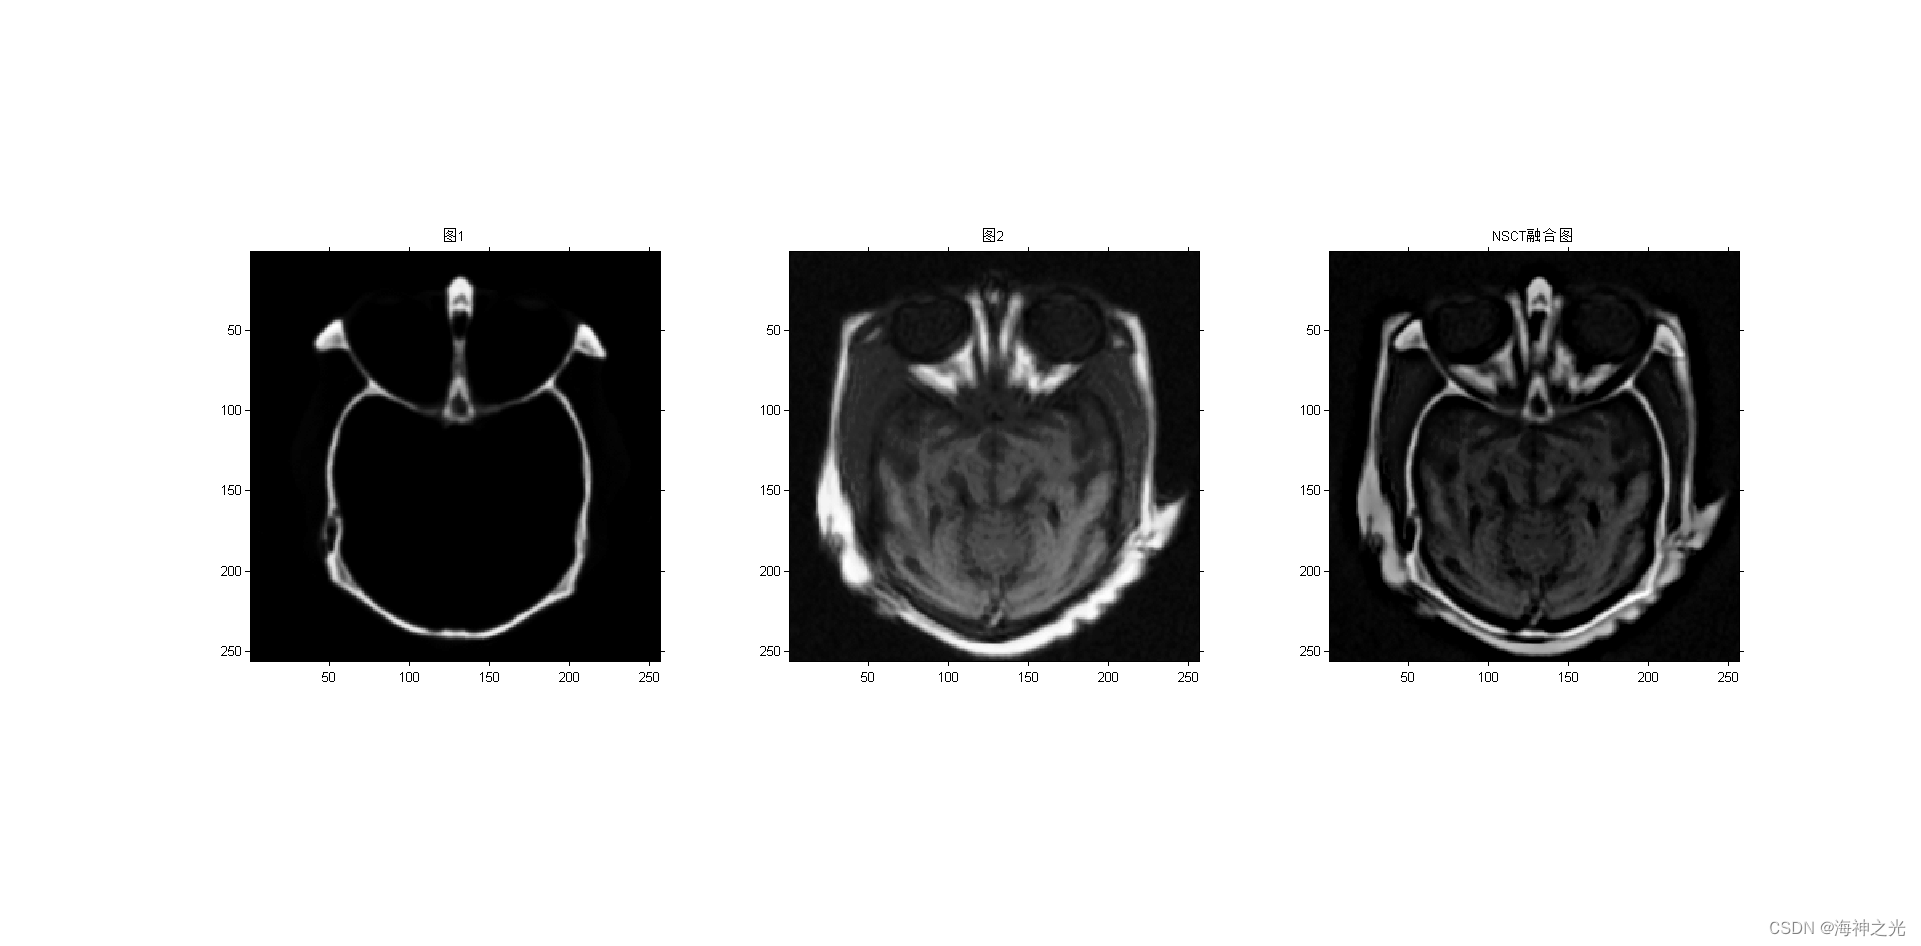

figure;subplot(131);imshow(image_input1);title(‘图1’)

subplot(132);imshow(image_input2);title(‘图2’)

F = nsct_fuse(A,B,[2,3,3,4]); %NSCT

title(‘NSCT融合图’)